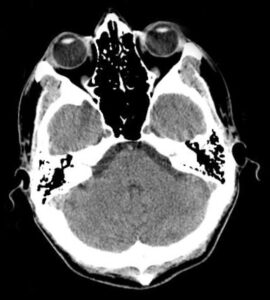

What Are Traumatic Brain Injuries?

Traumatic Brain Injuries are “disruptions in the normal functioning of the brain due to a bump, blow, jolt, or severe penetrating head injury.” Most injuries are mild, not severe, and result in concussions, while the more severe brain injuries can cause loss of consciousness, amnesia, permanent disability, or even death. According to the NY updated care plan for individuals suffering from TBIs, incidents of TBI are greater than incidents of HIV/AIDS, breast cancer, spinal cord injury, and multiple sclerosis combined. And in the United States alone, direct and indirect costs of TBI care and loss of income exceed $76 billion annually. Because the cost and impact of TBI is so great, making the understanding and prevention of TBI should be a priority.